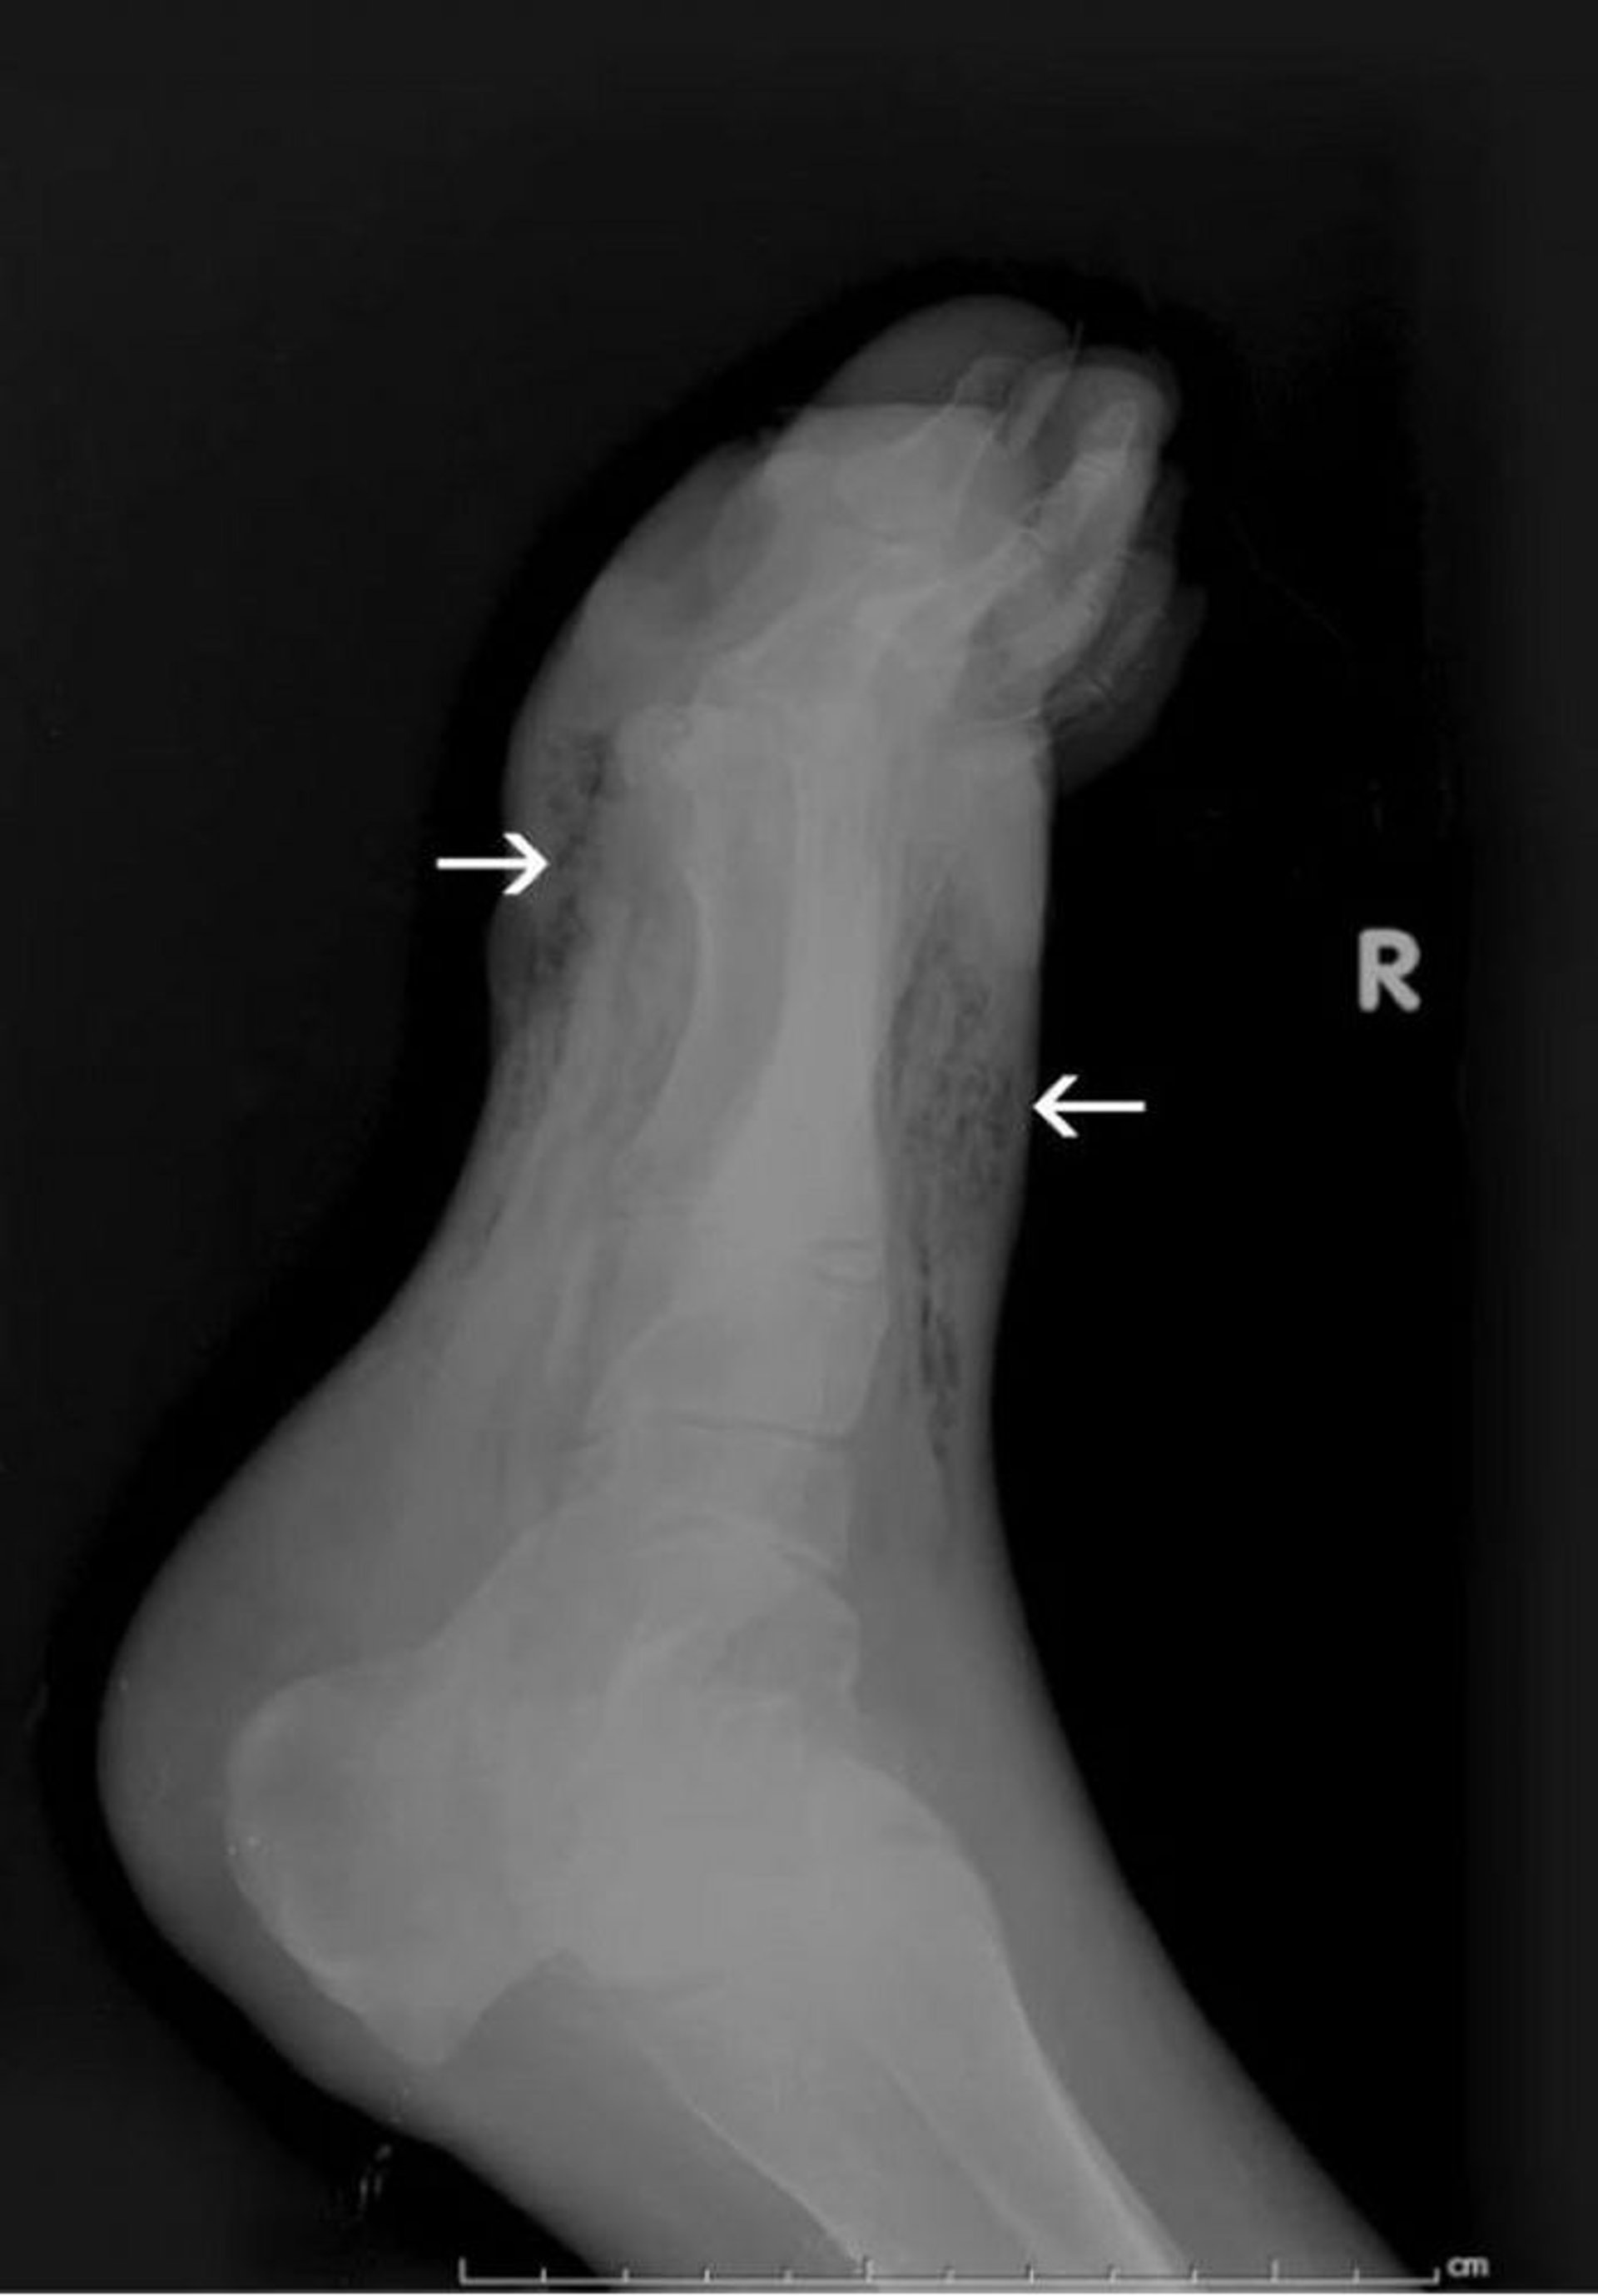

Hoại thư ở bàn chân (X-quang)

X-quang này cho thấy khí trong mô mềm của bàn chân (các mũi tên).